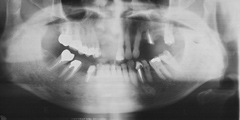

吉本歯科医院では、口内写真とパノラマレントゲンを撮影し、まずは顎の骨の状態まで詳しく確認しました。

(写真(1))虫歯の進行により歯の根っこに膿ができ、歯の周辺の骨まで溶け出している

・虫歯の進行により、歯の根っこに膿ができ、歯の周辺の骨までごっそり溶けてしまい歯がグラグラと揺れだした。

・親知らずを放置していたことにより、健全な歯を横に押し出し全体の噛み合わせ(咬み合わせ)のバランスを崩し、歯並びが悪く、不自然な力で噛み続けていたため歯が揺れだした。